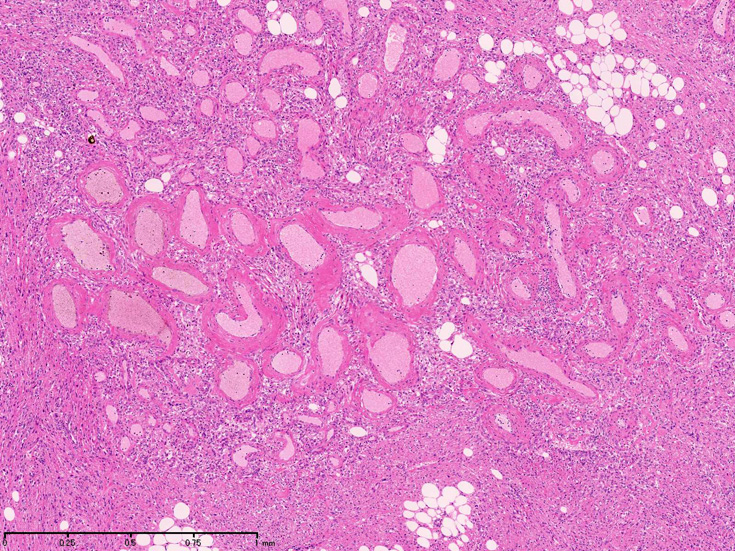

組織では血管, 平滑筋, 脂肪組織より構成され, 無秩序に混在する。

- 成熟脂肪組織はしばしばfat necrosis, lipophage, 巨細胞をともなって巨大腫瘤をつくるが, どの成分も主成分になりうる。

- 平滑筋細胞は血管壁外層と密接に関連しており同部位より発生しているように見える。筋細胞は放射状に配列し, 長円形核の長軸は血管に対して直角となるhair-on-end像を示す。

- 平滑筋はしばしば錯綜し束状に腫瘍全体を走行し島状の脂肪組織や血管集簇巣に中断される。糸球体内に腫瘍が増殖することもある。腎外病変も同様の組織所見を示す。